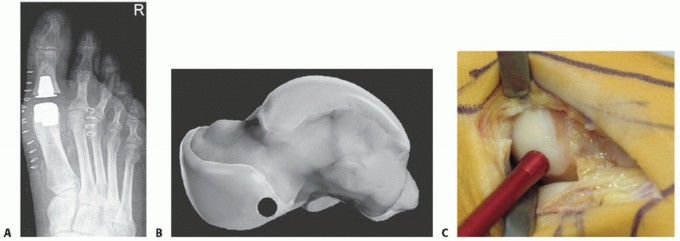

FIG 1 • A. Hallux rigidus grade 2 on AP weight-bearing radiograph. B. Hallux rigidus grade 3 on AP weight-bearing radiograph. C. MRI scan showing an osteochondral lesion of the metatarsal head.*

Standard weight-bearing anteroposterior (AP) (FIG 1A,B) and lateral radiographs of the foot as well as weight-bearing radiographs of the metatarsals and, in cases of sesamoid pathologies, a sesamoid special radiograph should be performed.

The MRI examination should include sagittal, axial, and coronal views with T1-weighted (TR 35 ms, TE 16 ms) and high-resolution gradient echo (TR 1060 ms, TE 16 ms) images (FIG 1C).